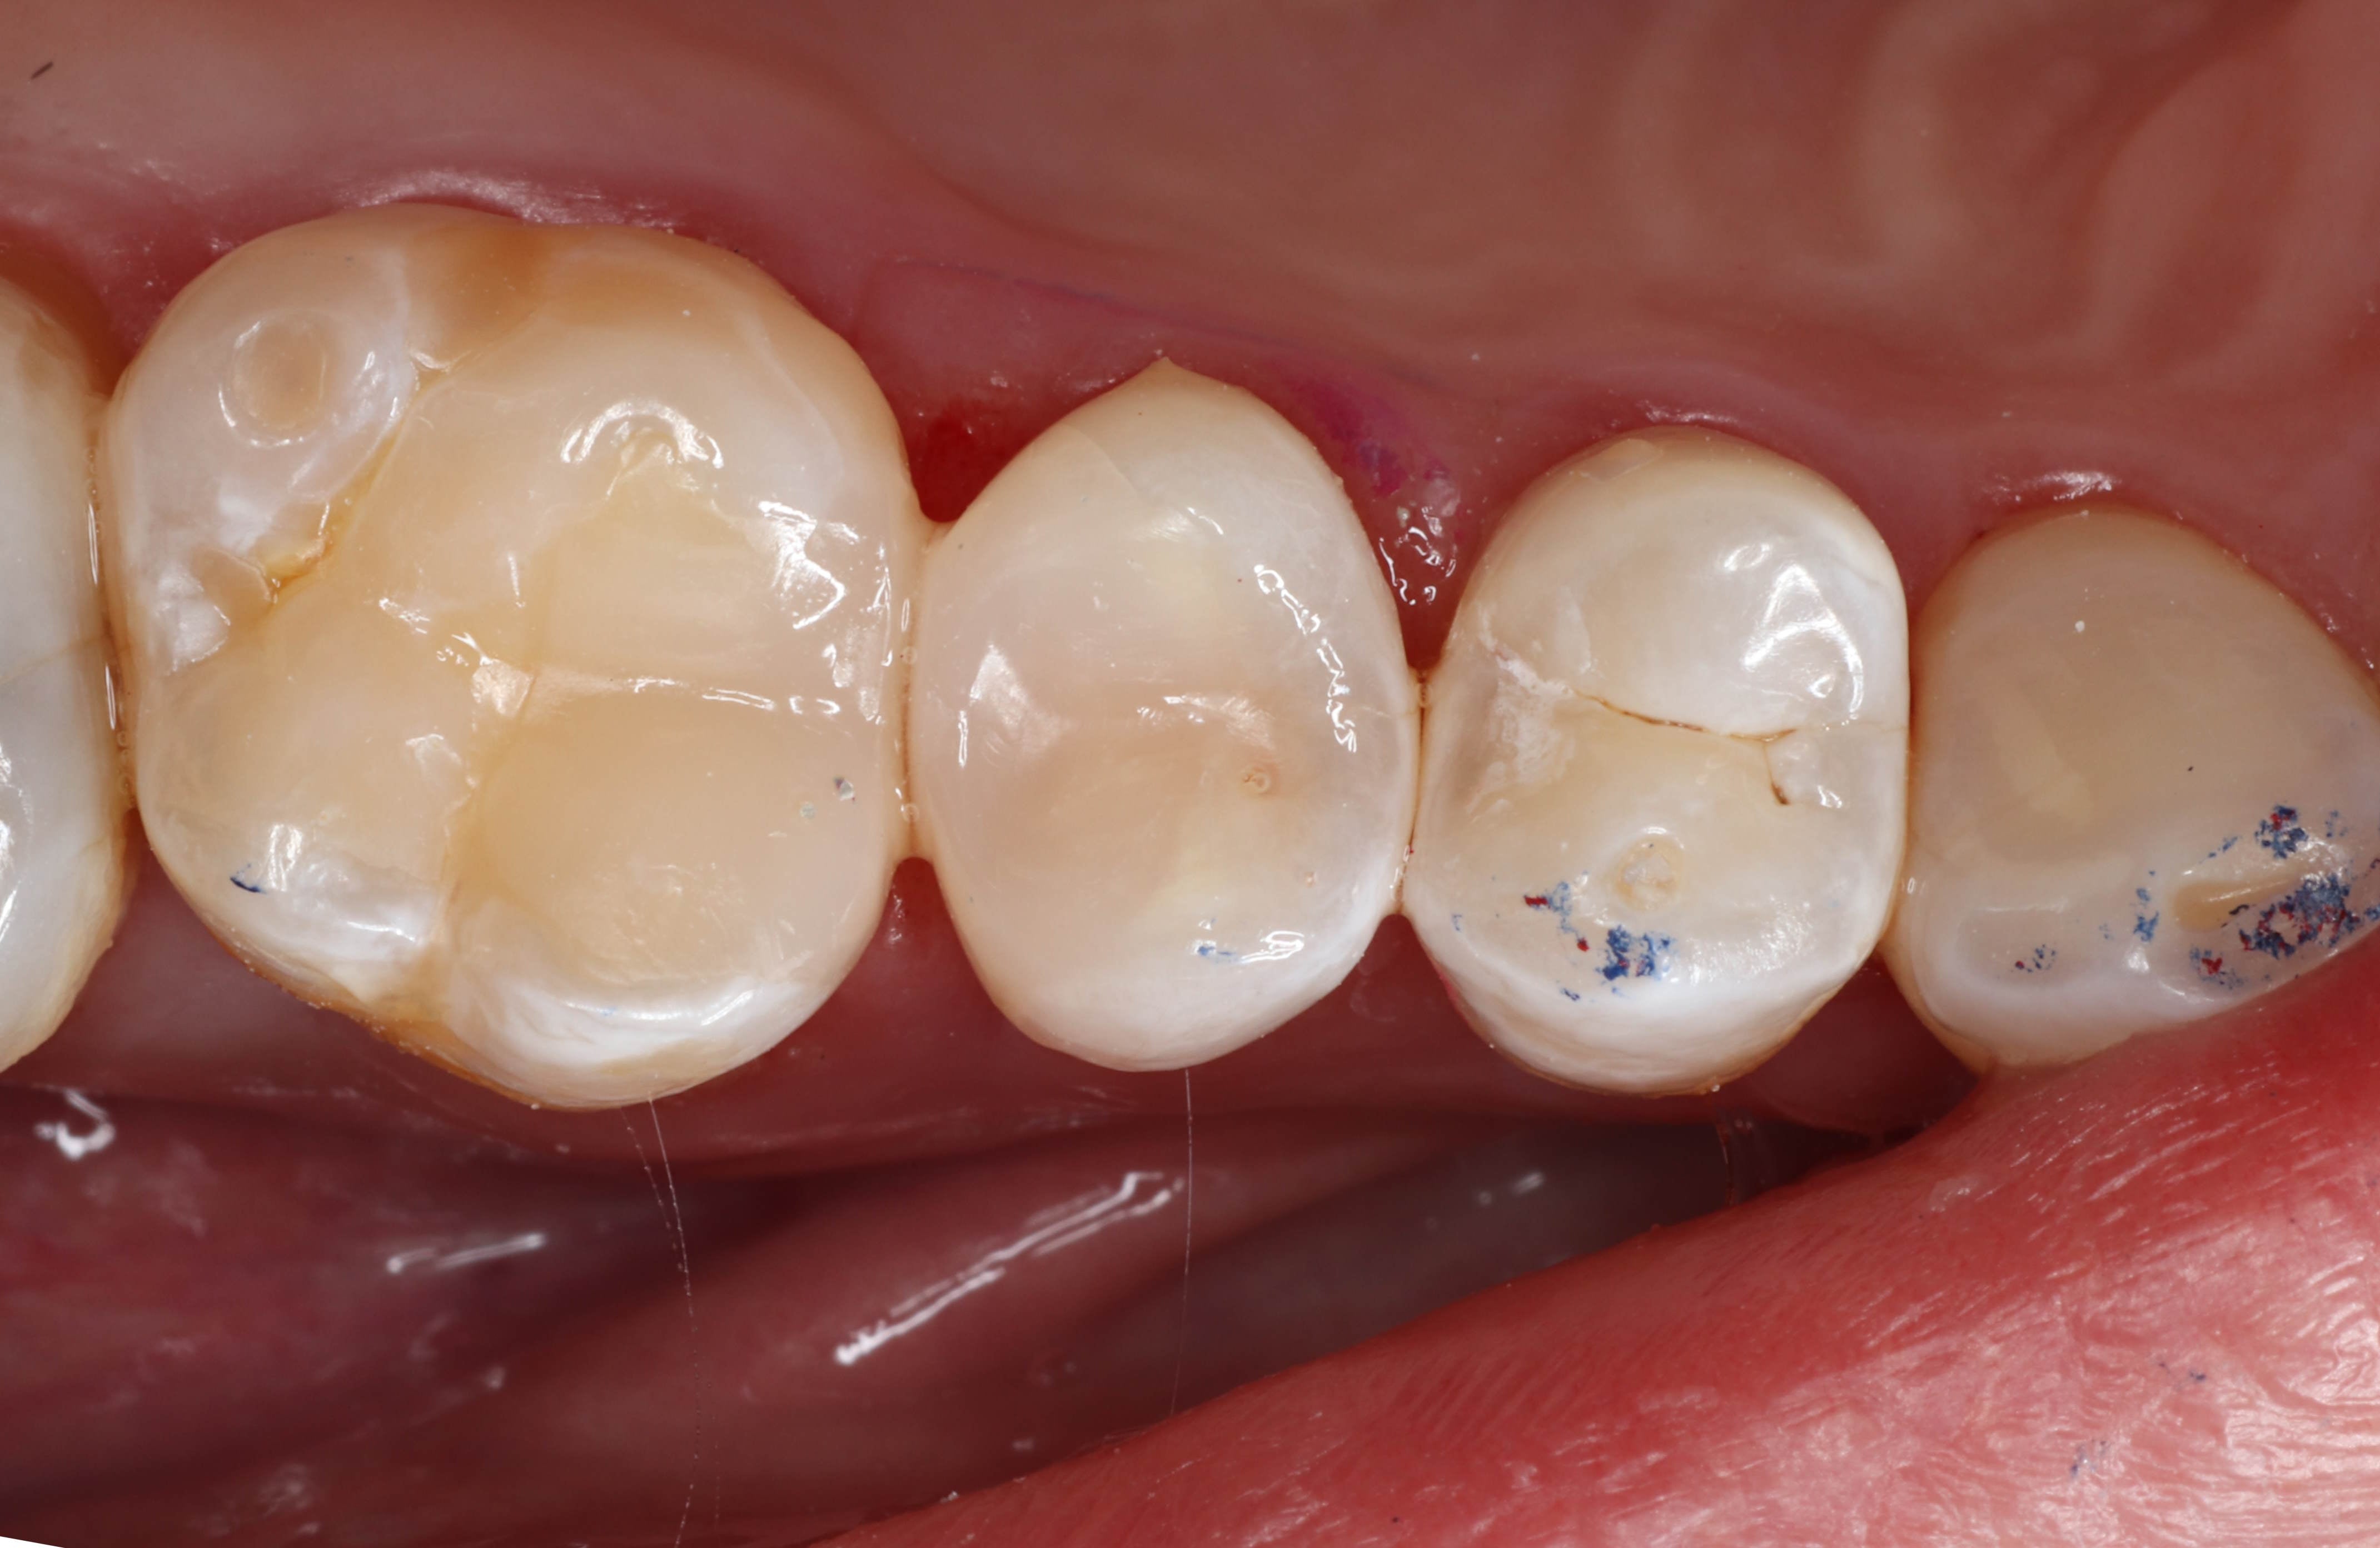

Class II

Class II restorations are a major part of dentistry, but up to 70% of dentists report inconsistent contact points, leading to sensitivity, food impaction, and recurrent caries.

The Bioclear Method addresses these issues with specialized protocols and the Evolve Posterior Matrix System. Bioclear's 75-micron Mylar matrices are anatomical, transparent, and designed for optimal morphology, precise contact points, heat injection-moulding, and effective light curing.

Stronger than metal matrices, they feature color-coded tabs for ease selection and placement, support bulk filling, and minimise finishing. The updated design offers 30% more bucco-lingual and occlusal wrap, accommodating cavities from shallow caries to deep bone-level cases, providing a reliable solution for Class II restorations.